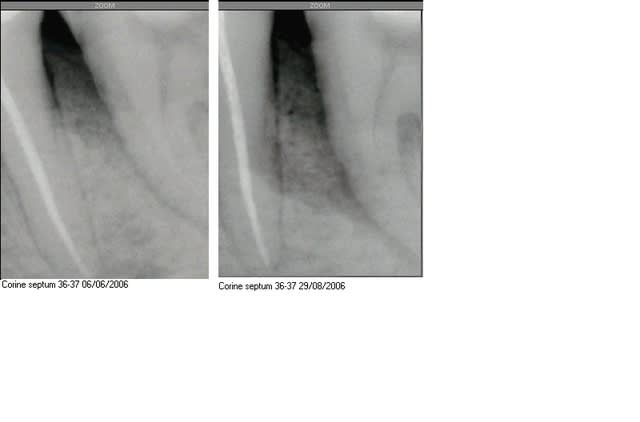

RDV pour détartrage, et voilà le résultat:

cicatrisation sur un septum absent ( "j'en ai perdu un bout, mais tout va bien maintenant")

Voilà les radios...

hum t aurais pas percé la racine avec le QS ?

Je dis ca en rapport avec la felure a midistance en distal de la racine

Tu m'inquiètes là...

Le dent est normalement sensible au froid, et pas à la percussion.

A bien y regarder je crains plus une parodontopathie agressive suceptible d'entrainer une carie radiculaire en fond de poche.... brrrr!